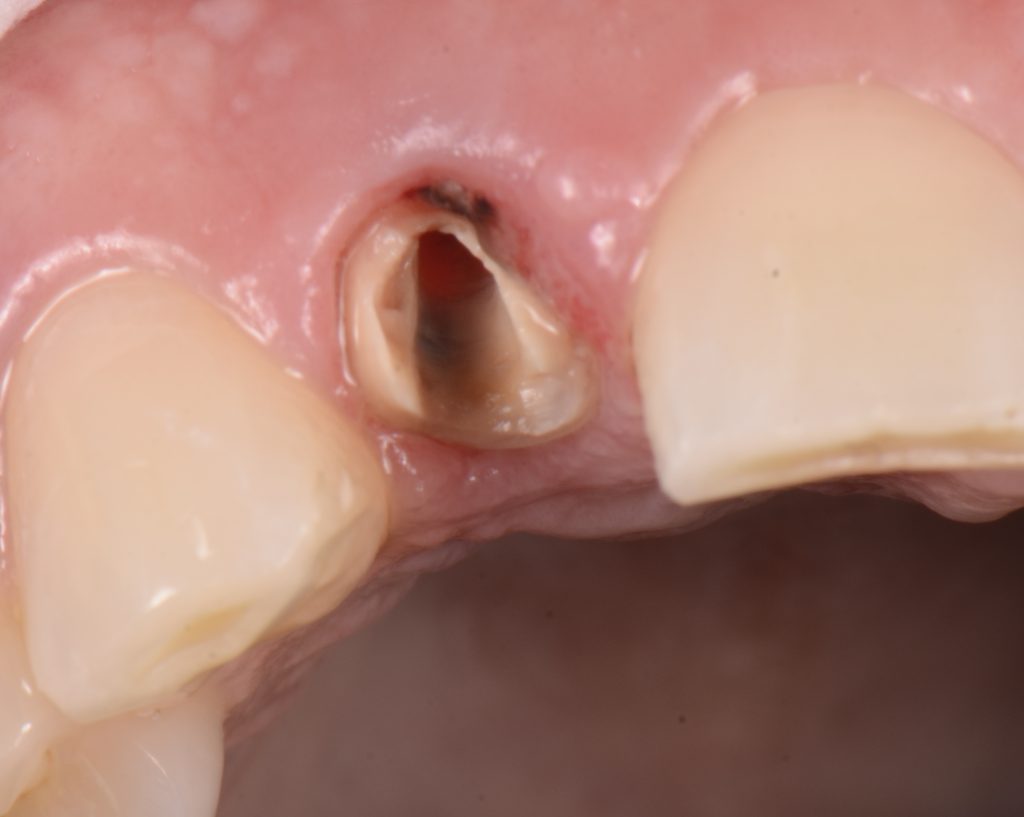

For instance, with dental crowns preliminary failure is when the luting cement seal clinically fails resulting in microleakage between the crown and the tooth (this preliminary failure is impossible to be initially detected clinically). Such microleakage will eventually cause a degradation, or washout, of the luting cement and may eventually be manifested as recurrent caries, loss of retention, fractured posts, or complete dislodgment of the crown and foundation restoration. (Figs. 3-4)

At this point the tooth or crown is most vulnerable to the heinous attack of soft bread.

This is also very common when the provisional cement on a temporary restoration is washed out, and suddenly, a soft, normally sticky bread will simply facilitate the dislodgement of the restoration.